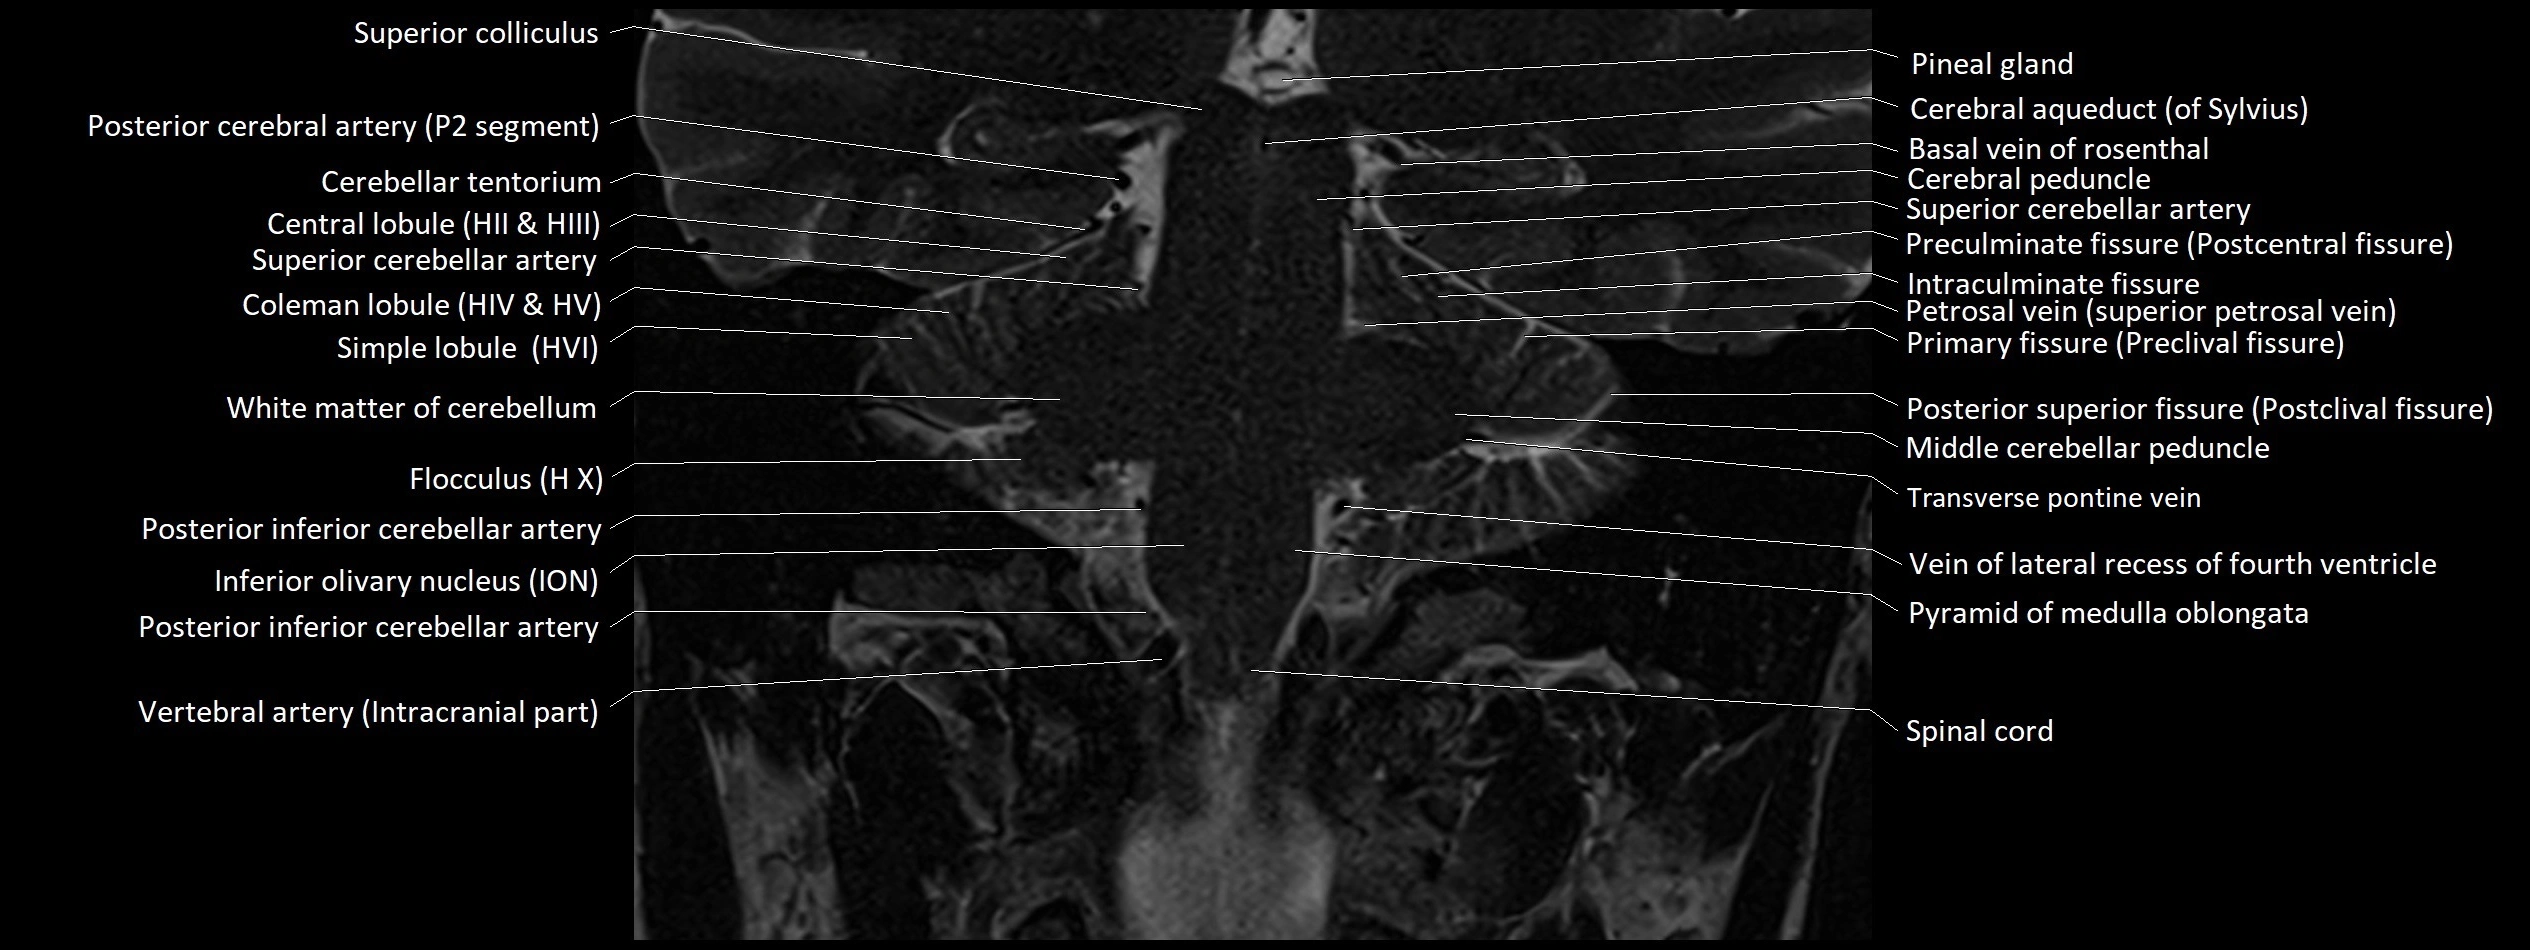

- Anterior lobe of cerebellum

- Biventral lobule (HVIII) of cerebellum

- Central lobule

- Central lobule (II & III) of Cerebellum

- Cerebellar tentorium

- Crus I of ansiform lobule of cerebellum

- Crus II of ansiform lobule of cerebellum

- Crus cerebri

- Declive

- Flocculus

- Middle cerebellar peduncle

- Paramedian lobule

- Paramedian lobule (HVII) of cerebellum

- Petrosal vein

- Pineal gland

- Posterior cerebral artery (P1 Segment)

- Posterior cerebral artery (P2 Segment)

- Posterior inferior cerebellar artery

- Posterior lobe of cerebellum

- Posterior quadrangular lobule

- Precentral cerebellar vein

- Preculminate fissure

- Primary fissure

- Simple lobule

- Simple lobule (HVI) of cerebellum

- Superior cerebellar peduncle

- Transverse pontine vein

- Transverse sinus